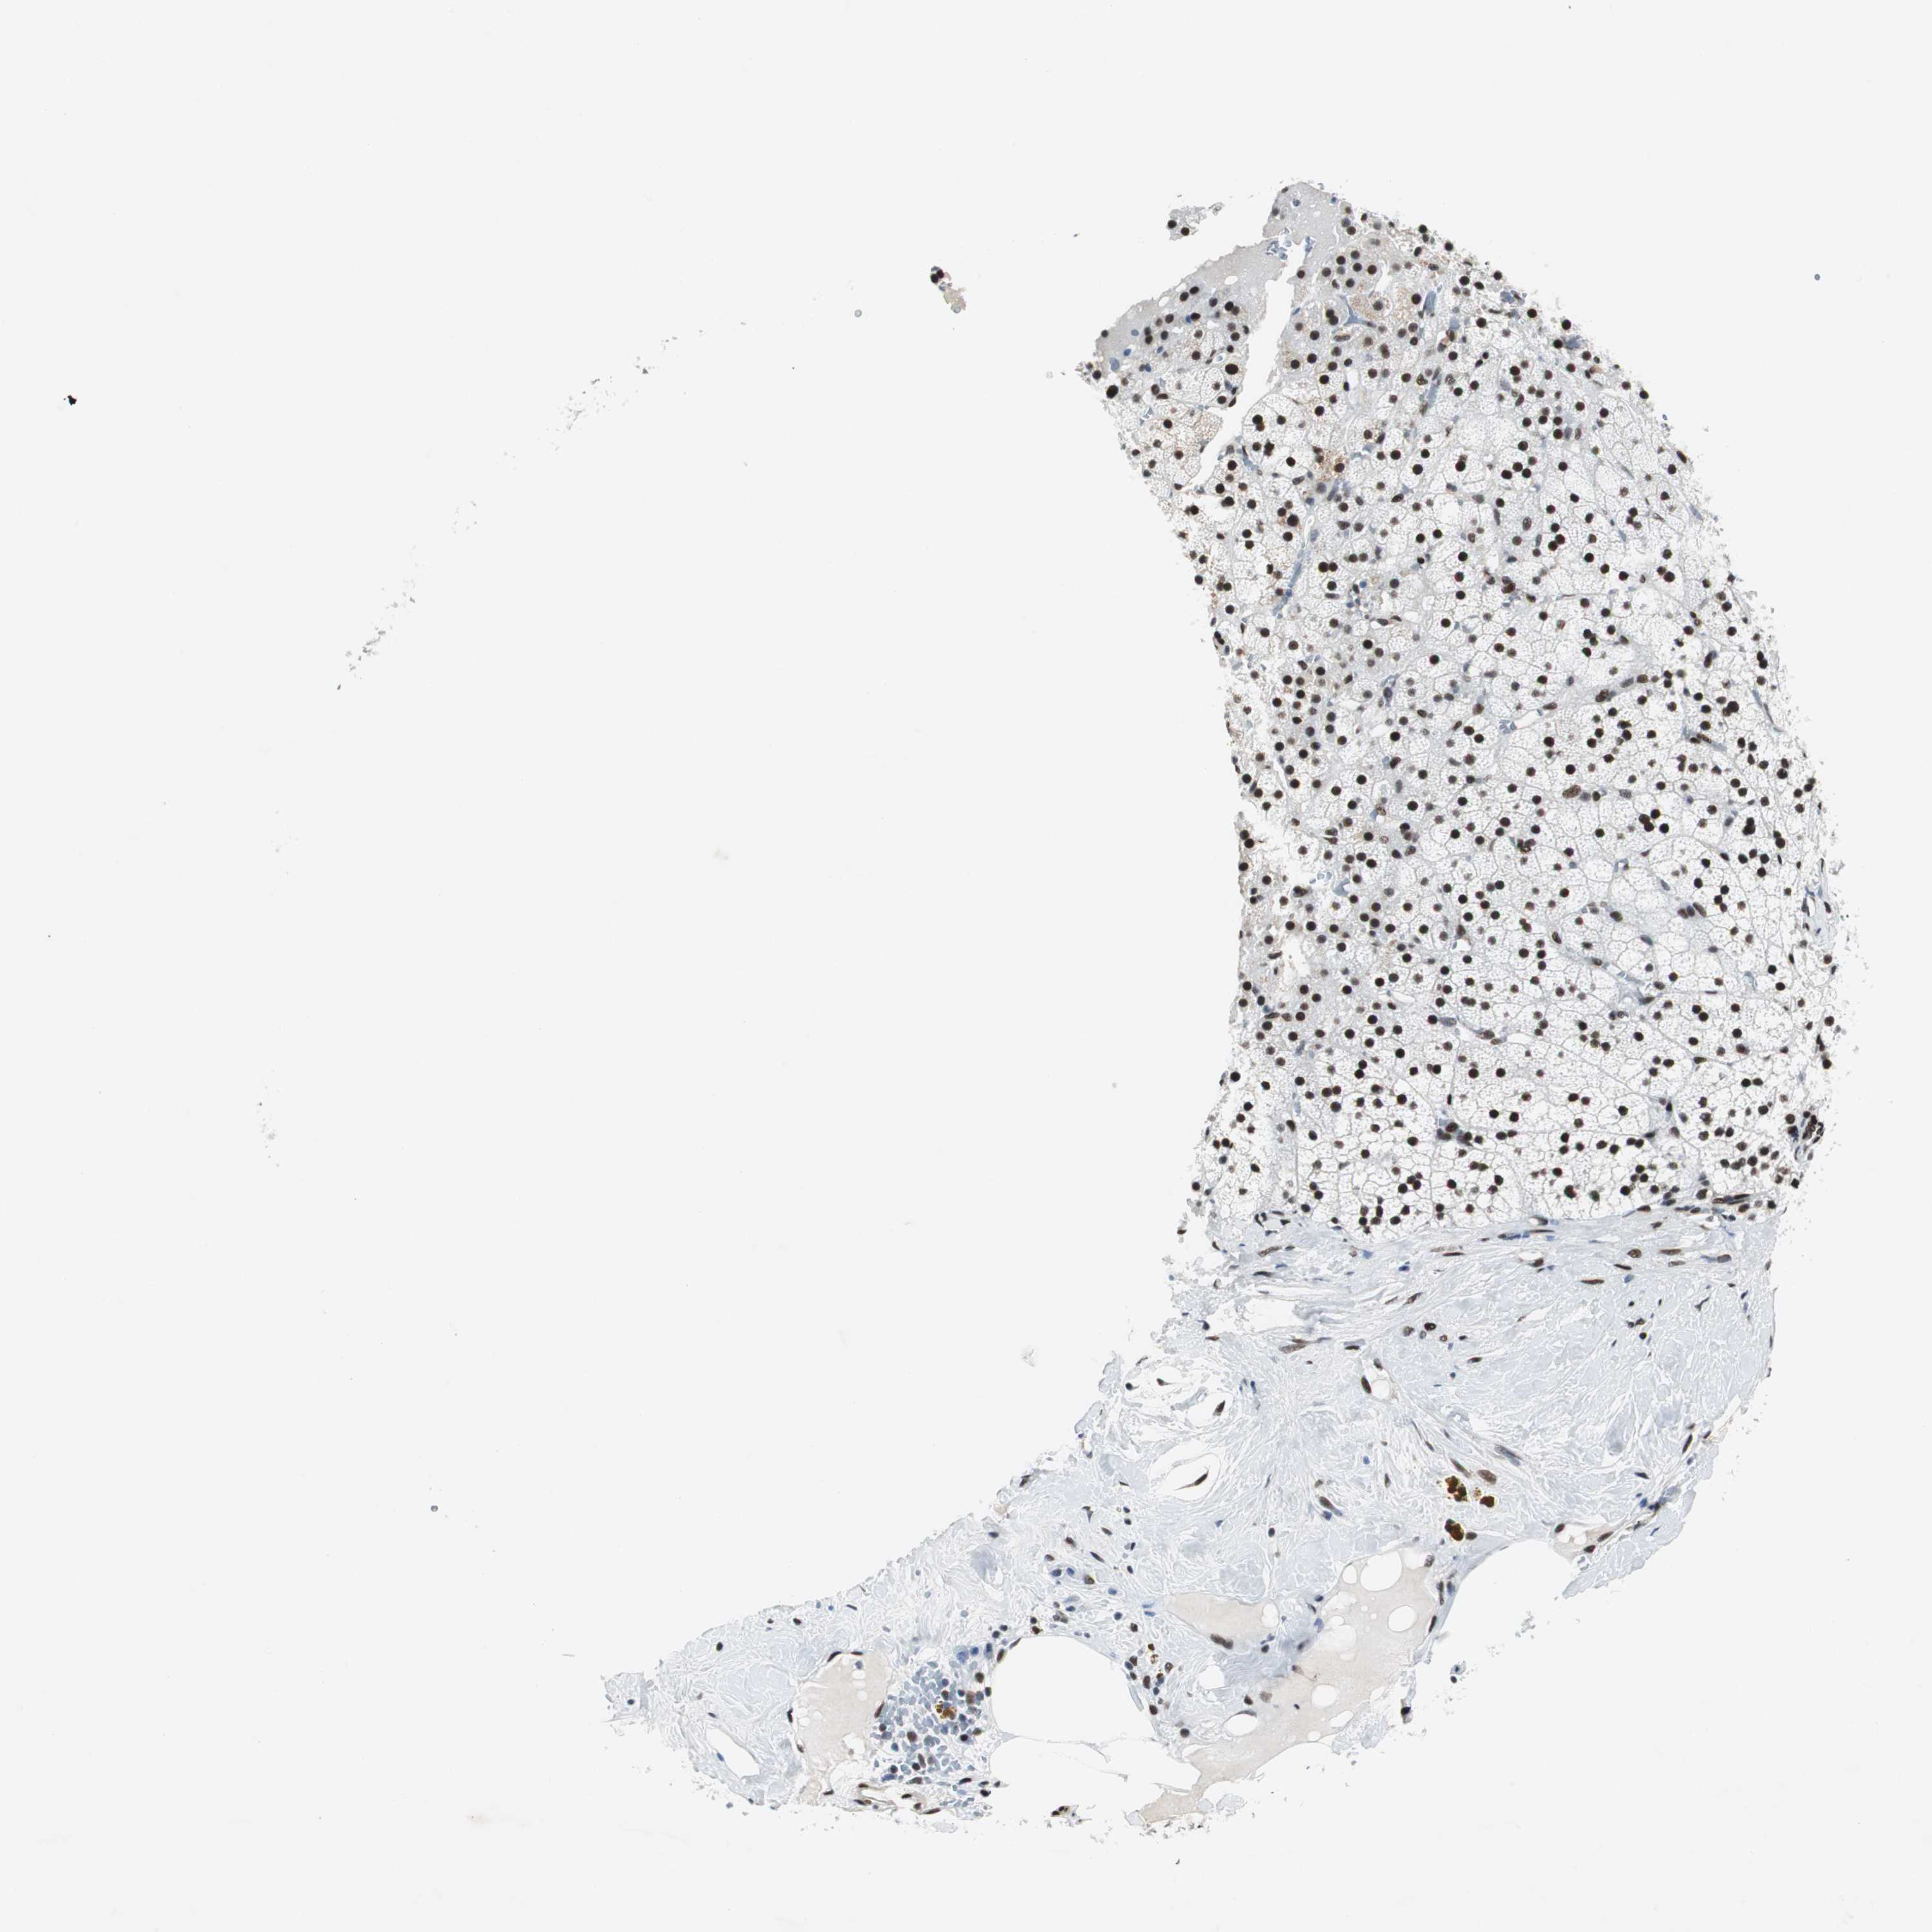

ADRENAL GLAND - Antibody stainingi

Antibody staining in the annotated cell types in the current human tissue is reported as not detected, low, medium, or high, based on conventional immunohistochemistry profiling in selected tissues. This score is based on the combination of the staining intensity and fraction of stained cells.

Each image is clickable and will lead to virtual microscopy that enables deeper exploration of all samples and also displays staining intensity scores, fraction scores and subcellular localization as well as patient and tissue information for each sample.

Antibody HPA004807Antibody HPA007114

Glandular cells HighHigh